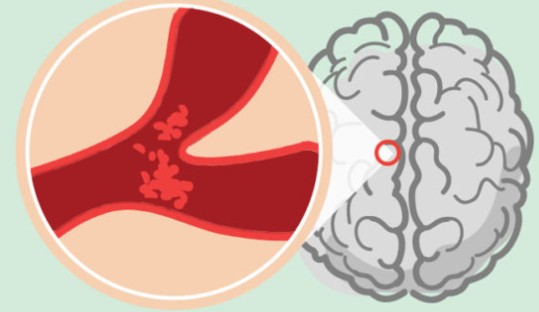

바로 **뇌졸중(중풍)**의 전조증상에 대해 알려드리려고 해요.뇌졸중은 뇌혈관이 막히거나 터지면서 뇌로 가는 혈류가 차단되어

신체 일부가 마비되거나, 심한 경우 생명까지 위협할 수 있는 응급질환입니다.

이 증상은 말을 관장하는 뇌 부위에 혈류 장애가 발생했을 때 나타납니다.5. 갑작스러운 시야 이상 (한쪽 시야 상실 등)

이런 증상은 눈 자체 문제가 아닌, 뇌에서 시각 정보를 처리하는 부위의 이상일 수 있습니다.

평소 두통이 없는 사람이 갑자기 벼락 맞은 듯한 극심한 두통을 겪는다면

뇌출혈(출혈성 뇌졸중)의 가능성이 높습니다.